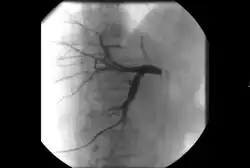

Ангиография: визуализация кровеносных сосудов для выявления аномалий с использованием различных контрастных веществ, включая йодированный контраст, вещества на основе гадолиния газ CO2 .[3]

ангиография артериита Такаясу